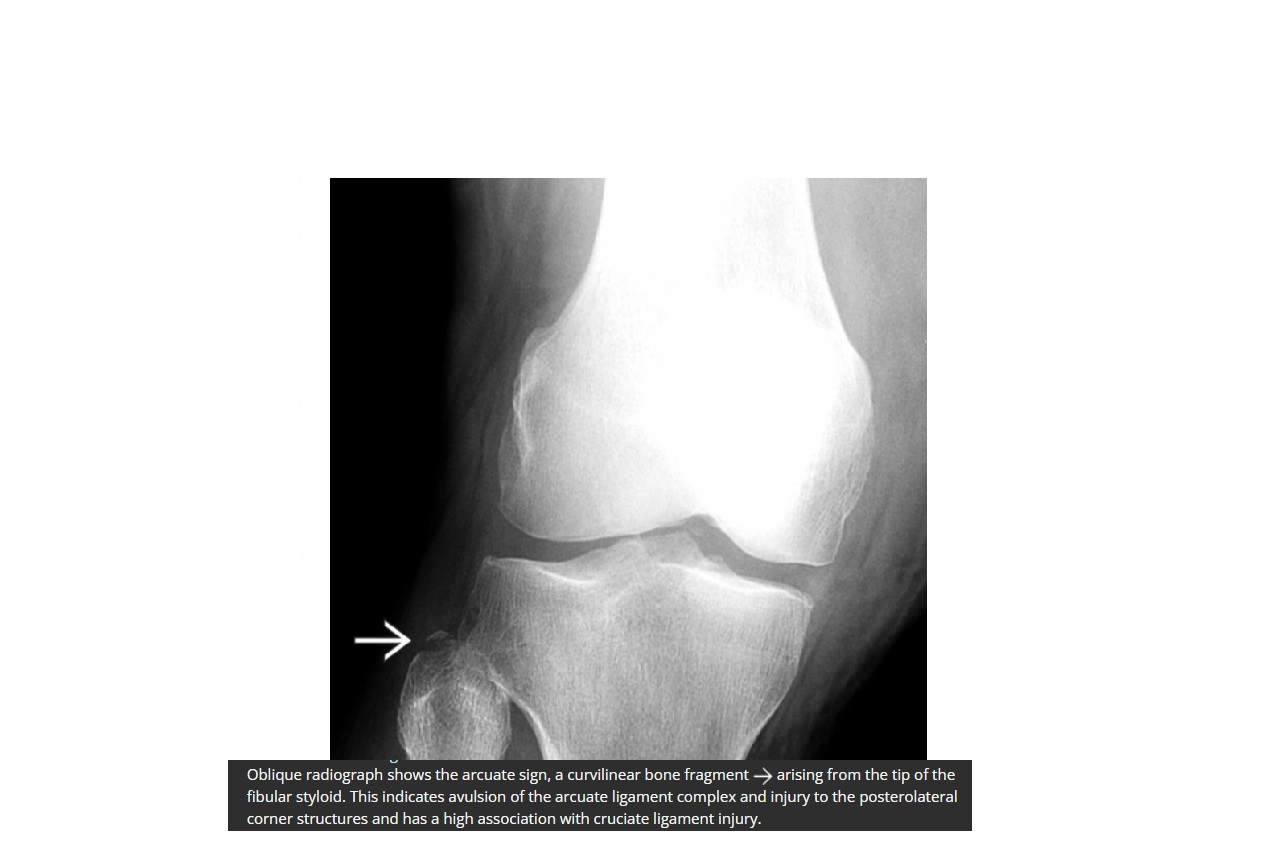

Arcuate sign

Avulsion of the proximal fibula

Associated with PCL tear